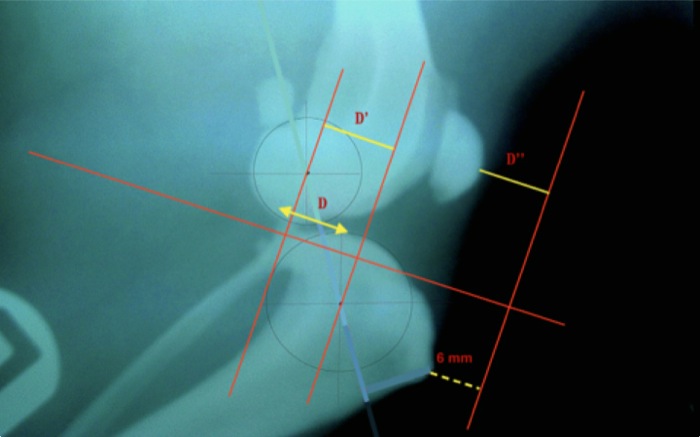

El primer paso tras la exploración son las radiografías a 135o con la subluxación reducida o bien corrigiendo la separación entre cóndilos y eminencia intertrocantérica (flechas, método del autor). La celda a elegir es decidida entonces. Hay estudios que determinan la celda en función del peso del perro. Se suele utilizar la celda mayor sin llegar a la fractura y ante dos tamaños de celda es mejor la más grande.

El objetivo del procedimiento es obtener durante la marcha un ángulo de 90o entre la meseta tibial y el tendón rotuliano principalmente en el momento de máximo esfuerzo sobre esta meseta tibial, ello ocurre con ángulos de 120o a 140o de ahí que las radiografías para las mediciones previas se realicen sobre una flexión a 135o.